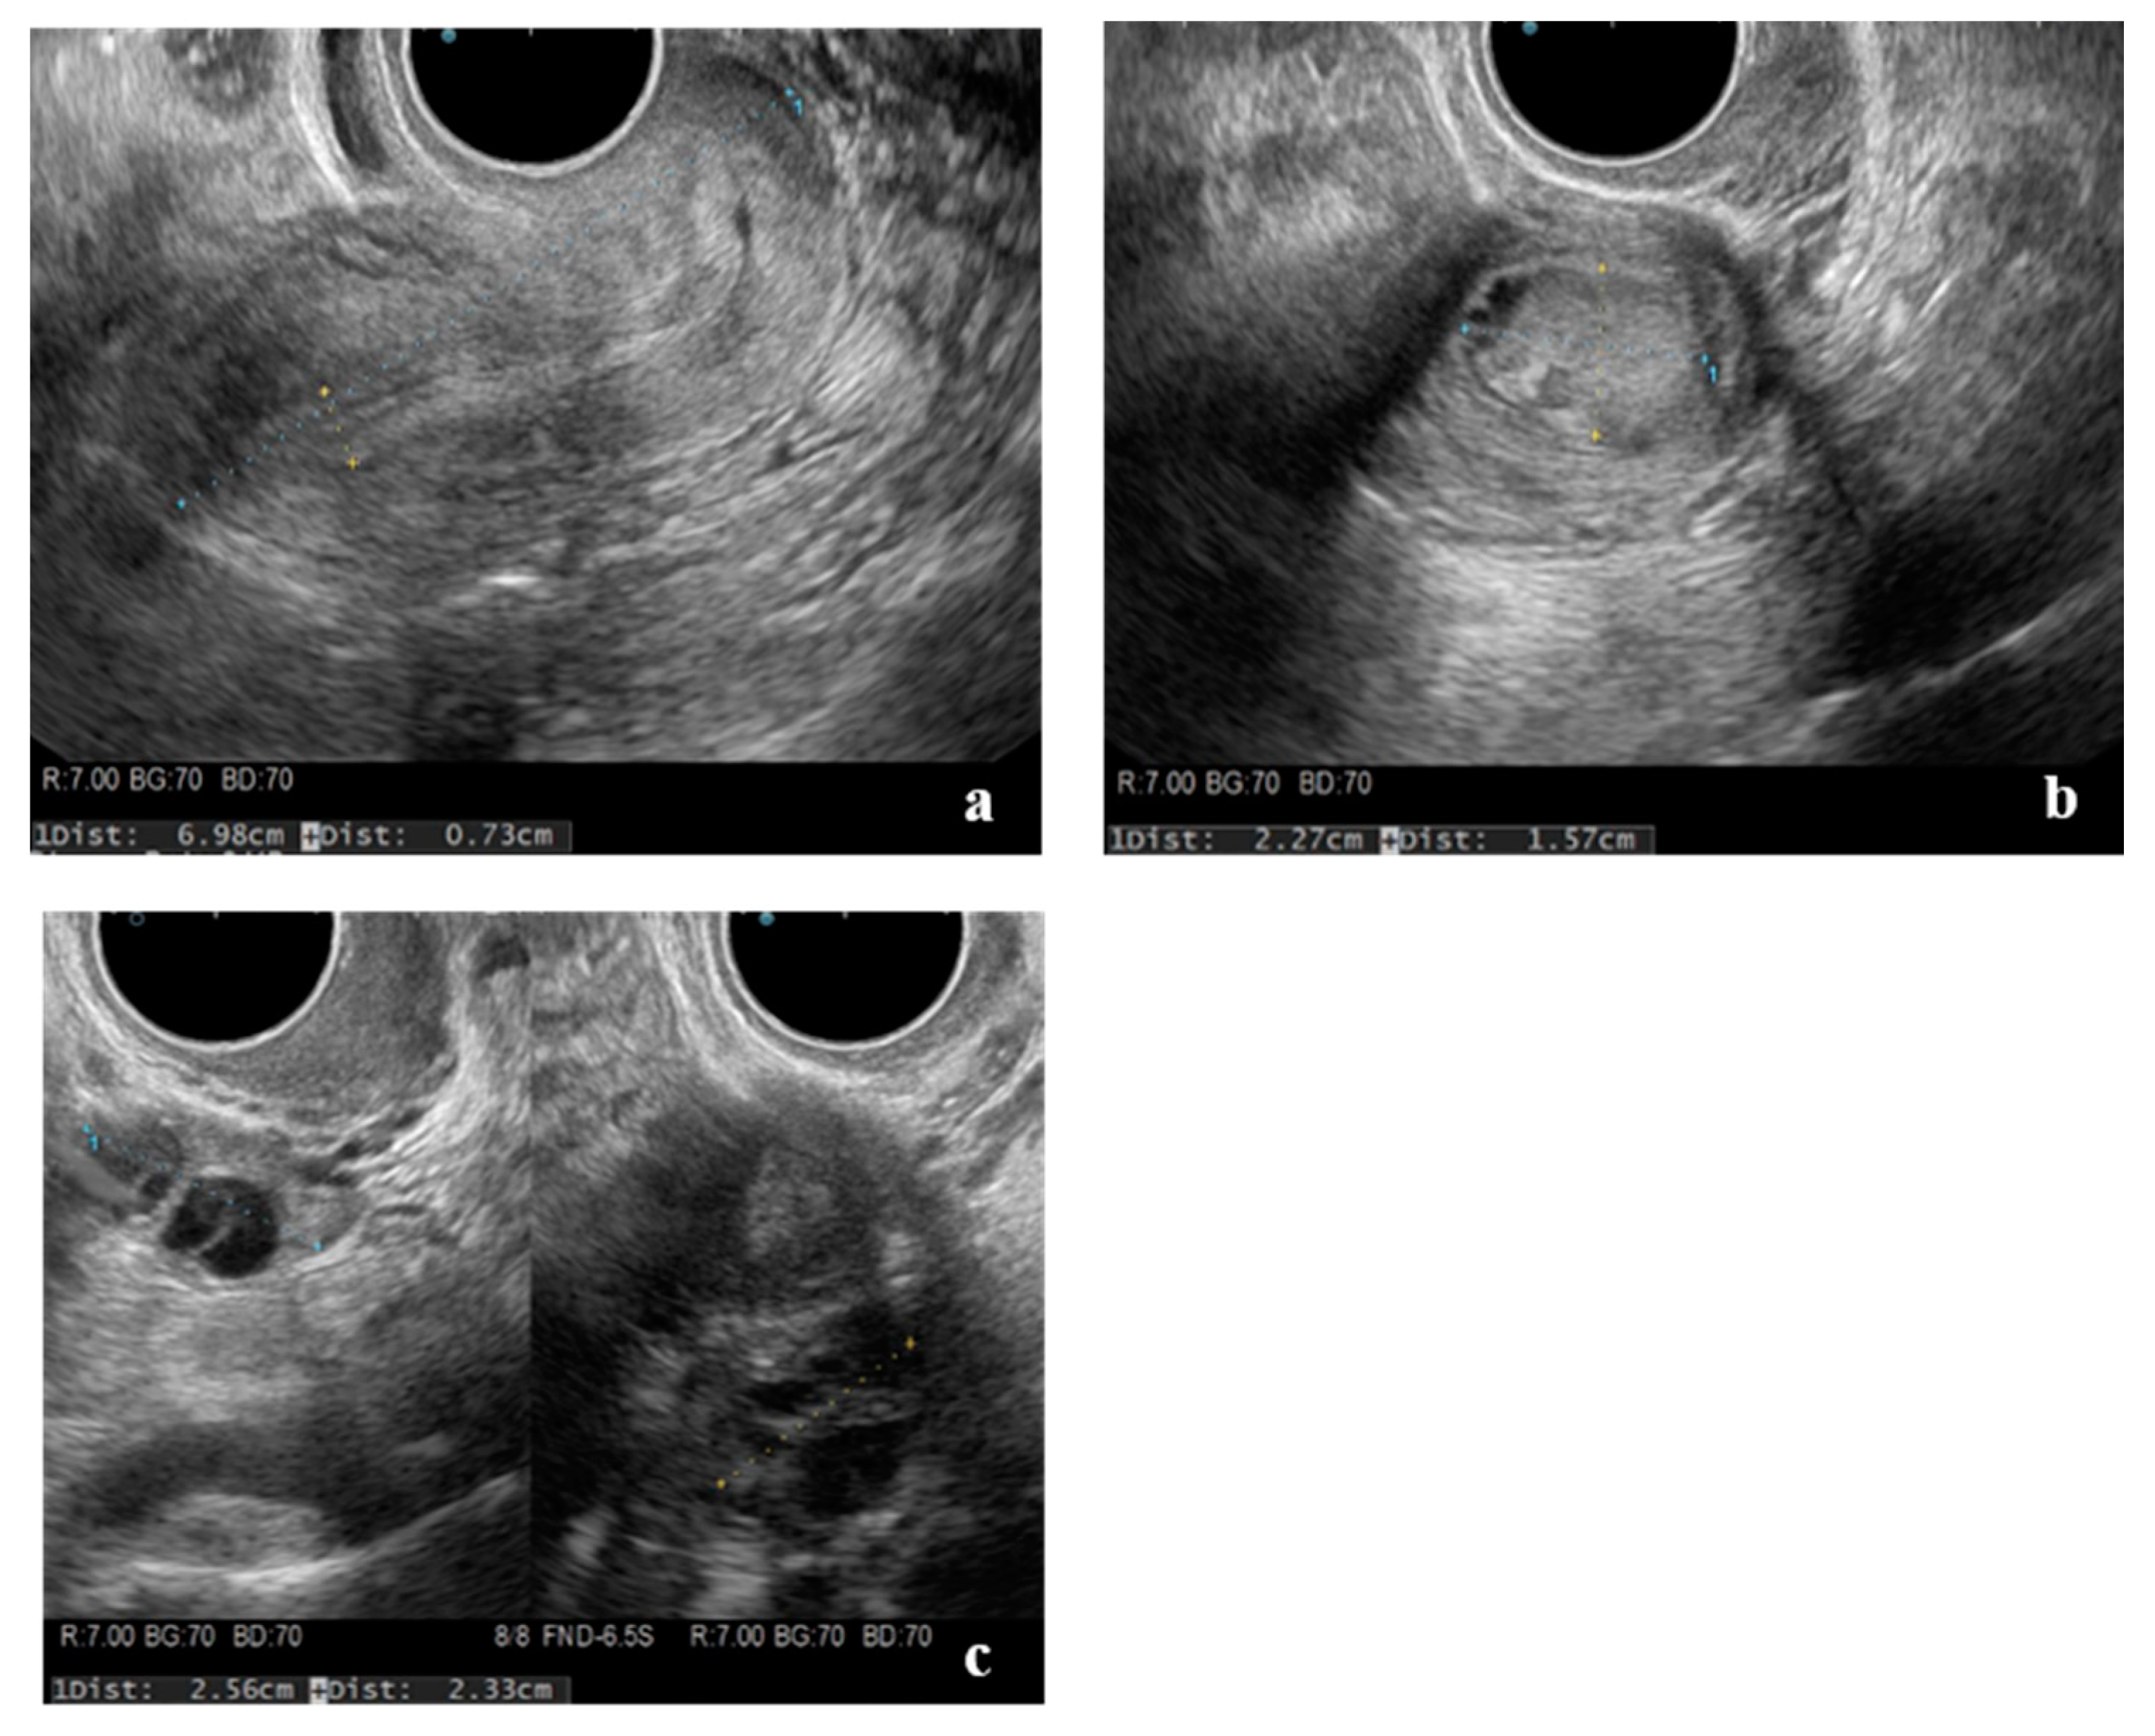

2. Case Presentation

| This case | 22 | 0 | 0 | 15 | 36 | L | 51.9 | None | CT, MRI: None | Laparoscopy | 3 cm, lateral, left side | Harmonic Scalpel, scissors forceps | 2 layers using 0 PDS | 14 | 69 | few | 2 | Present study |